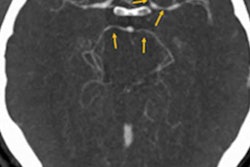

This 42-year-old male patient presented with axial neck pain and right upper-limb radiculopathy. Whole-spine T2-weighted sagittal screening images (a, b) show mild disk bulge at C5-6 (white arrow), and an intradural extramedullary tumor behind the body of L1 vertebra (black arrow). Image courtesy of Dr. Rishi Kanna and European Spine Journal.The group aimed to show how detailed images of the spinal column and adjacent spinal regions and paravertebral organ systems can reveal asymptomatic yet significant incidental findings.